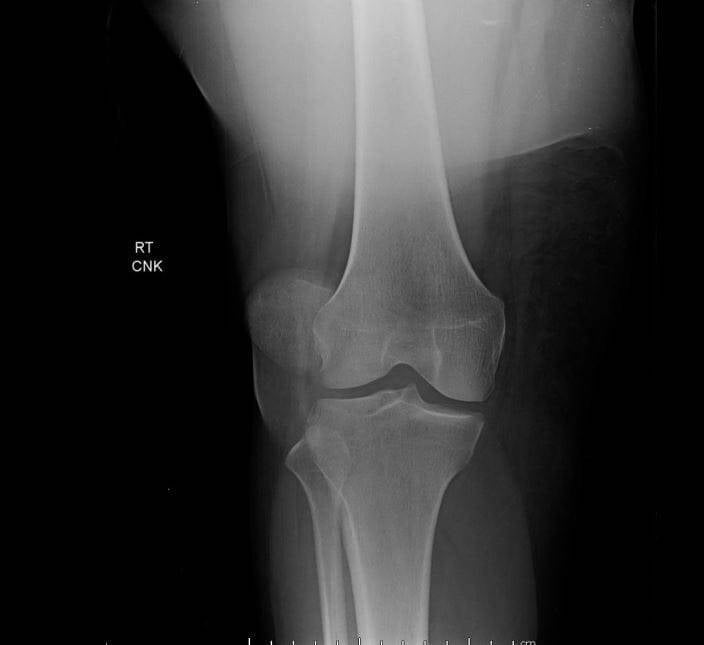

Se le hace una radiografía para descartar fracturas y dado su historial, se la deriva al traumatólogo de guardia, que recomienda la realización de una resonancia magnética. Los resultados muestran cierto desgaste en los meniscos; además de un leve desgarro en el ligamento patelofemoral medial.

Para el examen físico, se ejerce una presión lateral sobre la rótula empujándola así hacia afuera; que es la prueba de aprehensión rotuliana. Si el paciente muestra una postura defensiva o si el músculo del cuádriceps o reacciona intensamente, es signo de dislocación. También tenemos los estudios de imagen como la radiografía y la resonancia magnética (más precisa), que ayudan a examinar mejor la articulación de la rótula y sus estructuras circundantes; dándonos información sobre las posibles causas y evidencia de lesiones asociadas.